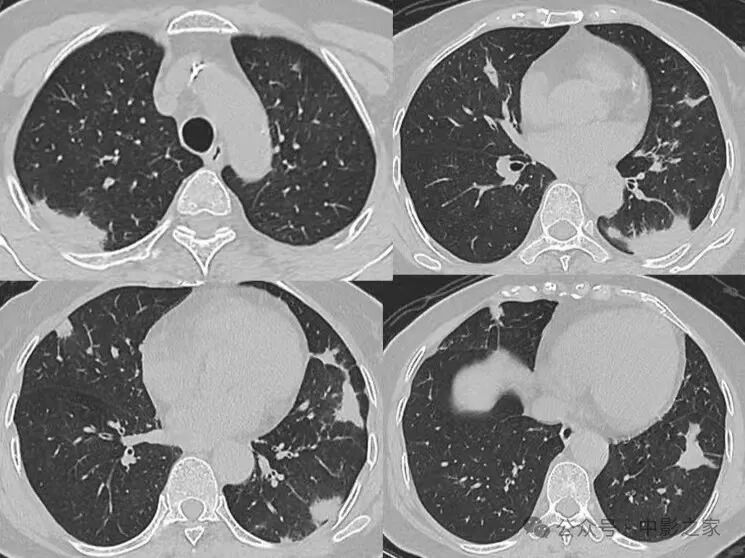

二、浸润实变型

1、分布多为下叶胸膜下

2、实变区密度均匀;

3、大部分病灶与胸膜相连(95%),糊墙征(个别可以栽赃)

4、晕征:大部分有,晕的大小不一致,相对而言实变区密度偏低的晕范围大一些,约20%无晕征;

5、实变区密度均匀或内部有片状低强化(各自占一半左右),且延迟强化;

6、实变区大部分边界清楚,有刀切征、平直征;20%边界稍模糊,30%周围有毛刺征;

7、含气支气管征与密度、晕征的关系:支气管可以直达远端,也可以近端堵塞,堵塞处支气管正常或稍扩张,走形正常;密度密实程度越高晕征越少,含气支气管近端堵塞的几率越高:如果周围晕征明显,密度偏低,边界欠清晰,含气支气管会直达远端;

8、空洞:约50%见到空洞或空腔,内壁光滑,可以多个组成,周围无坏死,内部无液平,可以有残余结构,个别内壁欠光滑;

9、近端均与血管相连。

四、混合型

混合病变,分布于肺外带,表现为结节、肿块、半片、大叶实变多样化病灶共存。